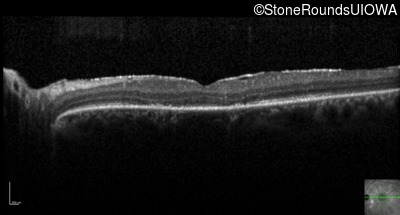

Optical Coherence Tomography - Right - 20/40 -2 sc

Exemplar / OCT Stack

Optical Coherence Tomography - Left - 20/20 sc